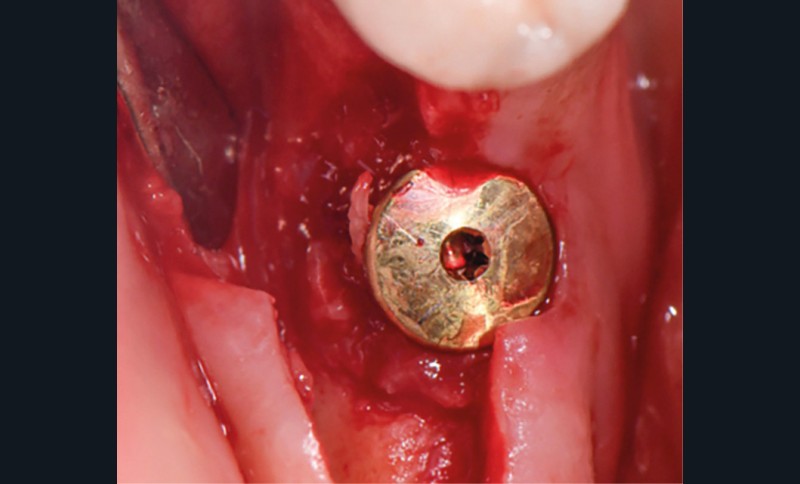

Actes préopératoires

La couronne a été déposée et une vis de couverture mise en place. La patiente a reçu un nettoyage supra-gingival général avec une attention particulière pour l’implant 47, et une irrigation locale avec du gel de chlorhexidine et du peroxyde d’hydrogène pour réduire l’inflammation des tissus. De l’amoxicilline (3 x 500 mg) a été prescrite, à commencer la veille de l’intervention chirurgicale.